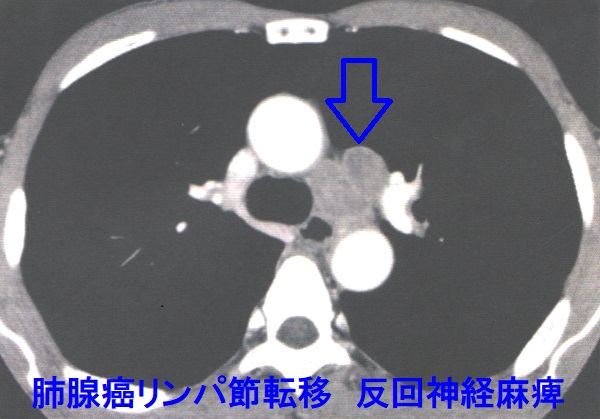

肺腺癌リンパ節転移 反回神経麻痺

肺腺癌リンパ節転移 CT画像;肺腺癌は末梢にできるため声のカスレ(嗄声、反回神経麻痺)を起こし難いですが、気管周辺の中枢測リンパ節に転移すると反回神経麻痺を生じます。